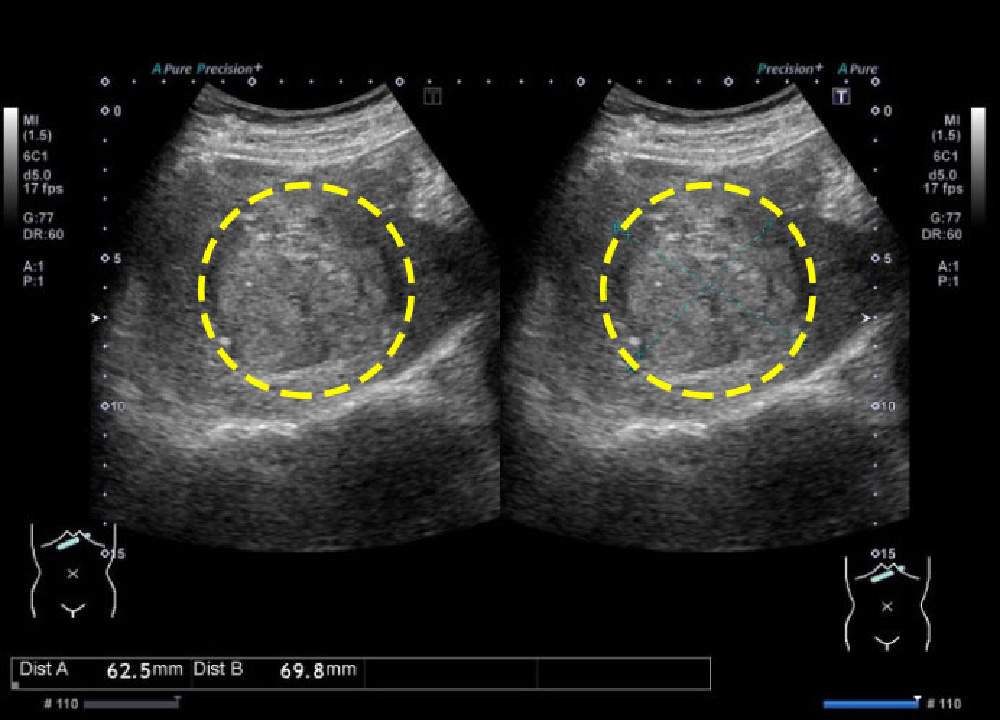

超音波検査で脂肪肝を,みて,見て,診よう 4。